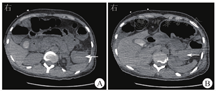

患者生命体征平稳,入院后未再次便血,暂予禁食水、补液、抑酸处理,给予200 mL氨甲环酸氯化钠注射液止血、2 U悬浮红细胞输注。2020年11月1日9:00复查血红蛋白为66 g/L,生命体征平稳,无便血,继续给予内科保守治疗并观察。11月2日4:22患者排大量(约500 mL)鲜血便,伴意识模糊,血压为57/35 mmHg,急查血常规示红细胞计数为0.85×109/L,血红蛋白为26 g/L,平均红细胞体积为93 fL,平均红细胞血红蛋白含量为30 pg,平均红细胞血红蛋白浓度为329 g/L。11月2日8:22急诊行第1次结肠镜检查,在直肠下段可见溃疡糜烂面,边界清楚,有黄苔附着,表面见大小约3.0 cm×2.5 cm的陈旧血块,未见明显活动性出血;进镜至回盲部观察3 min,未见血液从小肠流出;退镜过程中可见结肠腔内大量血凝块,反复冲洗未见新鲜出血(图2)。肠镜退出后20 min,患者再次排出大量(约500 mL)鲜血便,伴意识丧失。给予患者双通道加压补液、血管活性药物泵入、4 U悬浮红细胞输注、400 mL新鲜冰冻血浆输注后,收缩压上升至60~90 mmHg,意识稍有恢复。11月2日11:02急诊行全腹部+盆腔增强CT检查,动脉期、门脉期扫描示胰尾部与结肠间类圆形病灶明显强化,程度均与动脉相近,最大密度投影重建图像示病灶与脾动脉、结肠脾曲相连(图3A);延迟期扫描示结肠脾曲左侧肠腔内可见密度增高,提示肠腔内对比剂进入(图3B)。考虑脾动脉瘤破裂致结肠脾曲活动性出血。11月2日13:35行第2次结肠镜检查,进镜至结肠脾曲,可见黏膜隆起伴充血肿胀,顶端可见糜烂,有白色血栓头附着,未见活动性出血,以肠镜触碰血栓头可见鲜红色血液喷出(图4A);予以钛夹夹闭出血动脉,夹闭过程中可见大量活动性出血,6枚钛夹夹闭后暂无活动性出血(图4B)。结肠镜下止血后,患者仍持续排出少量血便(约80 mL/h),收缩压为80~100 mmHg。考虑动脉瘤破裂致结肠脾曲出血,钛夹止血不彻底,病因不能去除,仍有出血可能,遂于11月2日15:05行数字减影血管造影(digital subtraction angiography,DSA),可见脾动脉瘤样扩张,最大径为4.2 cm(图5A),证实为脾动脉真性动脉瘤,但未发现对比剂大量外渗,考虑因患者血压较低暂未出血或内镜下钛夹成功止血;在瘤体左侧可见结肠腔内的钛夹,证明存在脾动脉瘤结肠脾曲瘘。采用介入导管超选至脾动脉,置入6枚弹簧圈栓塞,再次造影未见对比剂溢出,动脉瘤不再显影(图5B)。11月3日患者排出少量血便,但生命体征平稳。术后1周复查增强CT示脾动脉栓塞术后,脾动脉瘤腔内未见对比剂进入,肠腔未见活动性出血。术后2周患者无便血、腹痛等不适,恢复进食后粪便常规和隐血试验均阴性,复查血红蛋白为97 g/L,康复出院。随访1.5年,患者未再便血,血红蛋白、血小板计数均在正常参考值范围内,粪便常规检查未见异常。